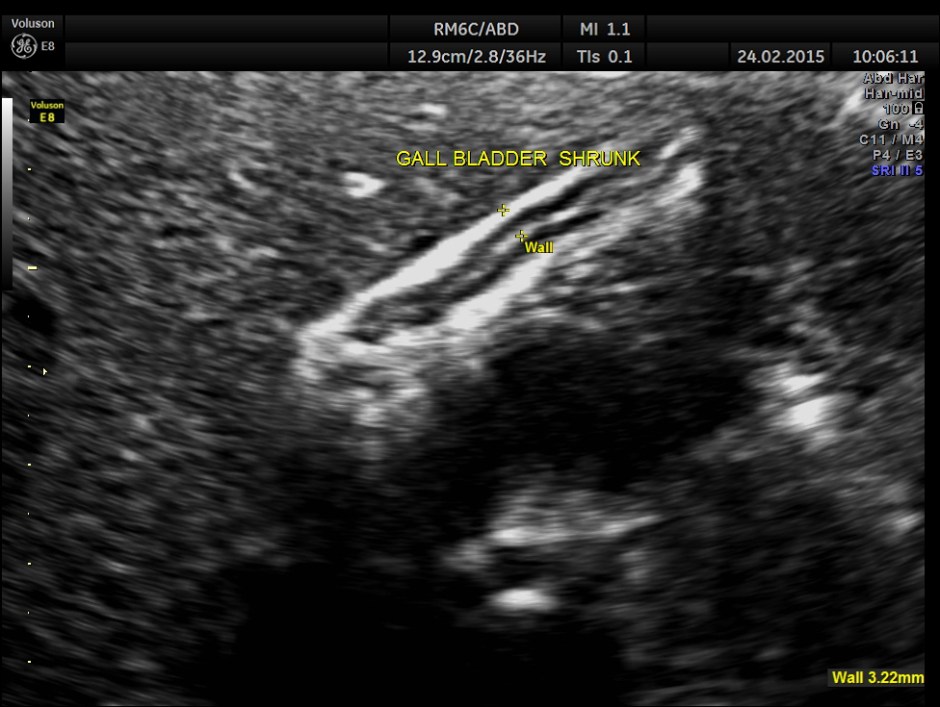

Completely collapsed and shrunk gall bladder in spite of over night fasting.

This patient probably had a functional gall bladder abnormality , asymptomatic at present.

Contrary to expectations she had a collapsed gall bladder in the fasting status and a partial filling up of bile after a fatty meal. As she had no symptoms , she was advised periodic follow up once in 6 months to start with.